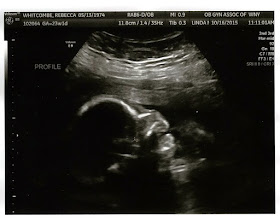

Feel like a broken record and the images are almost the same but can tell little by little he's getting bigger and bigger. Top pic is 3D image his little hands are in front of his face. Fluid was good, still lower than the normal but is getting more consistently up.